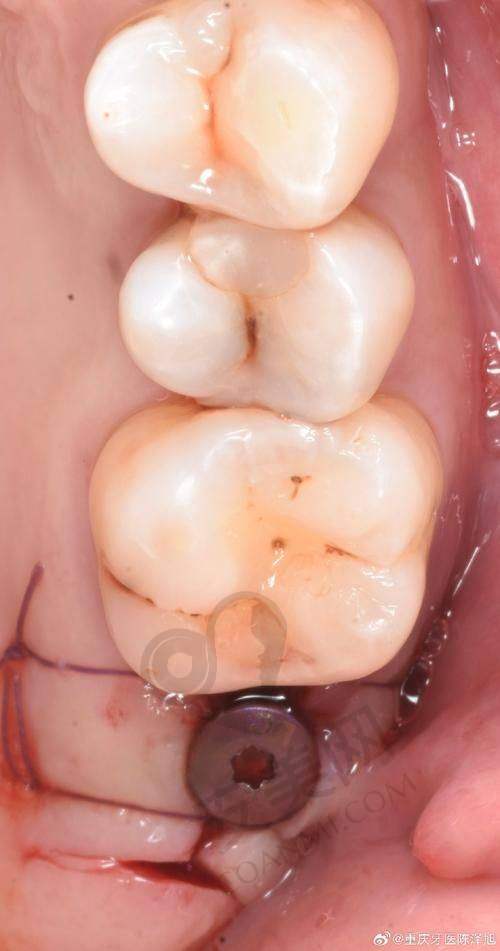

患者到深圳新浩口腔做美国皓圣种植牙,首先需要进行全方面的口腔检查。医生会通过口腔CT等设备,详细了解患者的牙槽骨情况、牙齿缺失情况以及口腔健康状况。根据检查结果,庄贤安医生会为患者制定个性化的种植方案,并向患者详细解释种植过程、可能出现的问题以及术后的注意事项等。如果患者同意种植方案,就可以进行种植手术。在手术前,医生会对患者进行局部麻醉,以减轻手术过程中的疼痛。手术过程中,医生会将种植体植入牙槽骨内,然后缝合创口。术后,患者需要按照医生的嘱咐进行护理,如服用消炎药、避免食用实力强的食物等。一般在种植体与牙槽骨结合稳定后,医生会为患者安装牙冠,至此整个种植牙过程就完成了。